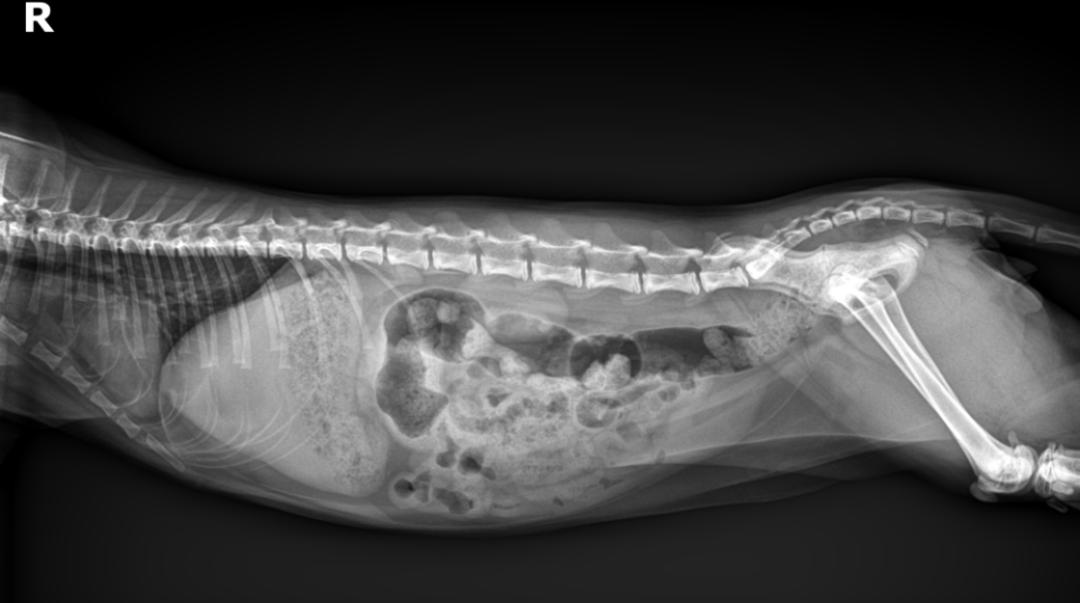

DR未显示高密度不透明征象

肠道积气严重

胃部有大量未消化食物

DR显示肠道胀气情况比上次有好转,

但是症状还是没有改善。